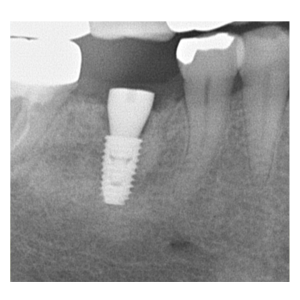

治療途中のインプラント症例

治療途中のインプラント症例です。

腫れ・痛み・神経損傷・インプラント周囲炎・骨吸収 など |